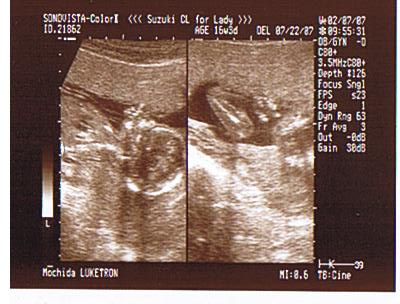

Molkata, nagyon szép kismama vagy azzal az édes pocival!!! Sajnos a mostani képen szinte csak a baba feje látszik, de majd megpróbálom felrakni ide vmikor...

Olyan jó lehet valóban tudni a nemét!!!